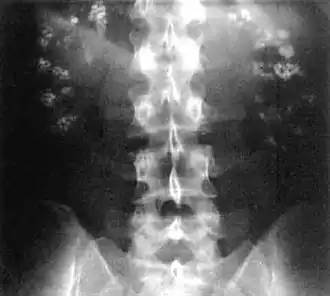

| Bilateral nephrocalcinosis seen on an abdominal x-ray | |

Nephrocalcinosis, once known as Albright's calcinosis after Fuller Albright, is a term originally used to describe the deposition of poorly soluble calcium salts in the renal parenchyma due to hyperparathyroidism. The term nephrocalcinosis is used to describe the deposition of both calcium oxalate and calcium phosphate.[1] It may cause acute kidney injury. It is now more commonly used to describe diffuse, fine, renal parenchymal calcification in radiology.[2] It is caused by multiple different conditions and is determined by progressive kidney dysfunction. These outlines eventually come together to form a dense mass.[3] During its early stages, nephrocalcinosis is visible on x-ray, and appears as a fine granular mottling over the renal outlines. It is most commonly seen as an incidental finding with medullary sponge kidney on an abdominal x-ray. It may be severe enough to cause (as well as be caused by) renal tubular acidosis or even end stage kidney disease, due to disruption of the kidney tissue by the deposited calcium salts.

Nephrocalcinosis is diagnosed for the most part by imaging techniques. The imagings used are ultrasound (US), abdominal plain film and CT imaging.[10] Of the 3 techniques CT and US are the preferred modalities.